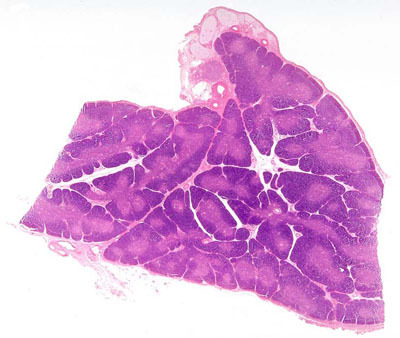

thymus